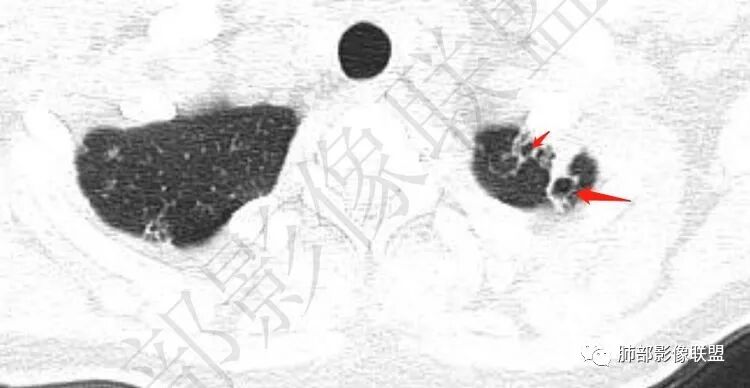

【每日晨读】双肺上叶多发薄壁空洞

年轻女性,血常规正常,体检发现,影像表现:双上肺多发空洞及空腔样改变,薄壁为主,部分壁不规则,伴不规则分隔,疑似鬼脸征,多数位于胸膜下。诊断:1、隐球,年轻女性,体检发现,血常规正常,多数胸膜下,疑似鬼脸征,必须首先考虑。2、结核,发病部位支持,多发空洞样病变支持,但无临床症状,病灶形态太单一,无树芽征,可能性不大。3、PLCH,无吸烟史,无临床症状,可能性小。4、寄生虫,无嗜酸增高,无IGE增高,可能小,5、空腔性转移,无原发灶,年轻较小,暂不支持。6、多中心原发腺癌,空腔周围无明确边界清楚的GGO,年轻。可能小。7、NTM,无支扩,可能小。8、风湿类疾病,无相关病史,无相关自身抗体结果,暂不支持。综上,考虑隐球菌可能大。先查隐球荚膜抗原。必要时穿刺活检。

大雄: 青年女性,双上肺多发不规则薄壁空洞伴少许结节,部分洞内有分隔,病灶多位于胸膜下,无症状,血象正常。影像比较怪异,可能得疾病谱有:隐球,结核,寄生虫,NTM,类风湿结节,空洞型转移,PLCH结核无明显气道播散树芽,寄生虫嗜酸细胞不高,NTM无症状,类风湿结节与转移少见上叶优势分布,PLCH一般有吸烟史。综上,先考虑隐球菌,建议查隐球抗原

2.双肺多发薄壁空洞影、条索影及结节影,边界较清楚,密度偏高不柔和,散乱,但有成簇倾向或堆积感,胸膜下分布为主,双肺上叶分布为主。

3.空洞相当不规则,缺乏张力,未见血管穿行,未见壁结节,未见液平。

1.年轻女性,缺乏临床表现,多发空洞及结节影、条索影,上肺胸膜下分布为主,临床实践中常见肺病是什么?正如部分老师分析的—继发性肺结核!